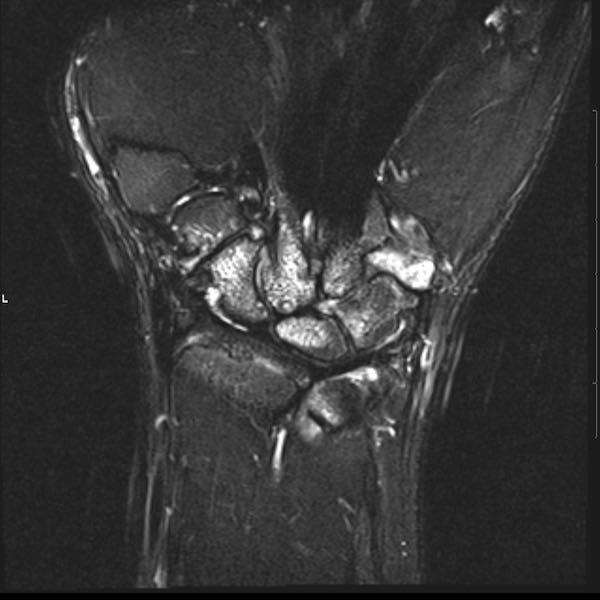

Tiếp tục xem hình ảnh MRI của bệnh nhân này.

Hình ảnh MRI:

Tràn dịch lan tỏa tất cả các khớp cổ tay.

Phù tủy xương lan tỏa tất cả các xương cổ tay.

Bào mòn xương, ví dụ tại xương thuyền, xương đầu và xương móc.

Phá hủy khe khớp và sụn khớp, rõ nhất tại khớp STT và CMC4/5.